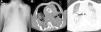

Verificou-se rápida deterioração clínica com falência respiratória grave, refratária a terapêutica médica otimizada e ventilação não invasiva (gasimetria: Ph 7,14; pCO2 74mmHg; pO2 32mmHg; SO2 41%; lactatos 5,4mmol/L). Pela impossibilidade de entubar e ventilar o doente, e após várias tentativas de entubação orotraqueal com apoio de broncofibroscopia, foi realizada traqueostomia percutânea emergente. A antibioterapia foi então alterada para vancomicina e imipenem, e por hipotensão arterial refratária à administração de volume iniciou suporte inotrópico. O Rx do tórax revelou infiltrado difuso e a tomografia axial computorizada (TAC) do tórax evidenciou focos de consolidação parenquimatosa bilateral, densificação em «vidro despolido» e derrame pleural bilateral (Figura 4).

Radiografia do tórax infiltrado parenquimatoso bilateral e lesões nodulares dos tecidos moles em relação com lipodistrofia (A) e imagens da TC do tórax ao nível da prótese aórtica, janela mediastínica (B) e janela de pulmão (C), focos de consolidação parenquimatosa bilateral, densificação em «vidro despolido» e derrame pleural bilateral.